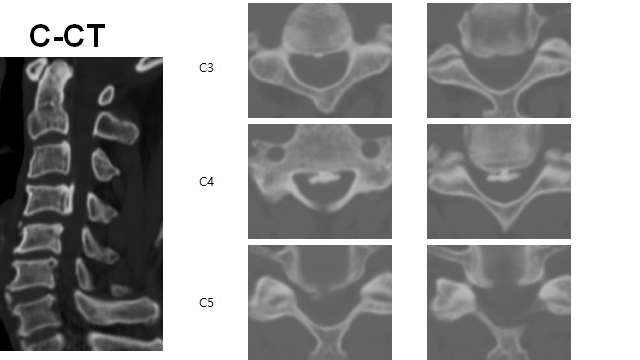

HCD C3/4 4/5 c OPLL C4 with cord compression

ACDF C3/4/5 + VBSO(vertebral body sliding osteotomy) C4